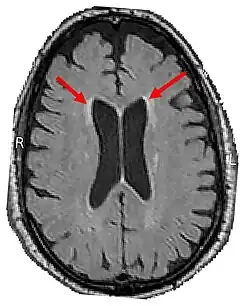

LENAS is seen with damage to the white matter and axons within the brain. The external human LENAS brain shows findings in several major structures. There is mild atrophy of the frontoparietal regions of the brain and a mild reduction of the thalamus and rostral (front) part of the caudate nucleus (which is located in an area of the brain called the basal ganglia).[5] Abnormalities in the frontal, frontoparietal, and temporal lobes are most severe and predominant with LENAS and asymmetry of the cerebral hemispheres has sometimes been found.[5] LENAS also may show moderately enlarged lateral ventricles and atrophy in corticospinal tracts as well as in the pons.[5]

The area where it is seen to be the most pronounced abnormalities appear in the white matter below the pre- and postcentral gyri that extend through the posterior limb of the internal capsule into pyramidal tracts of the brain stem.[5]

- Longitudinal MRI studies annually can potentially also help with prognosis. This was found from another study which found that, as throughout the disease course, the more rapid the confluence of patchy or focal T2-weighted hyperintensities and the progression of cortical atrophy suggests the poorer the prognosis appears to be.[13][14][12]